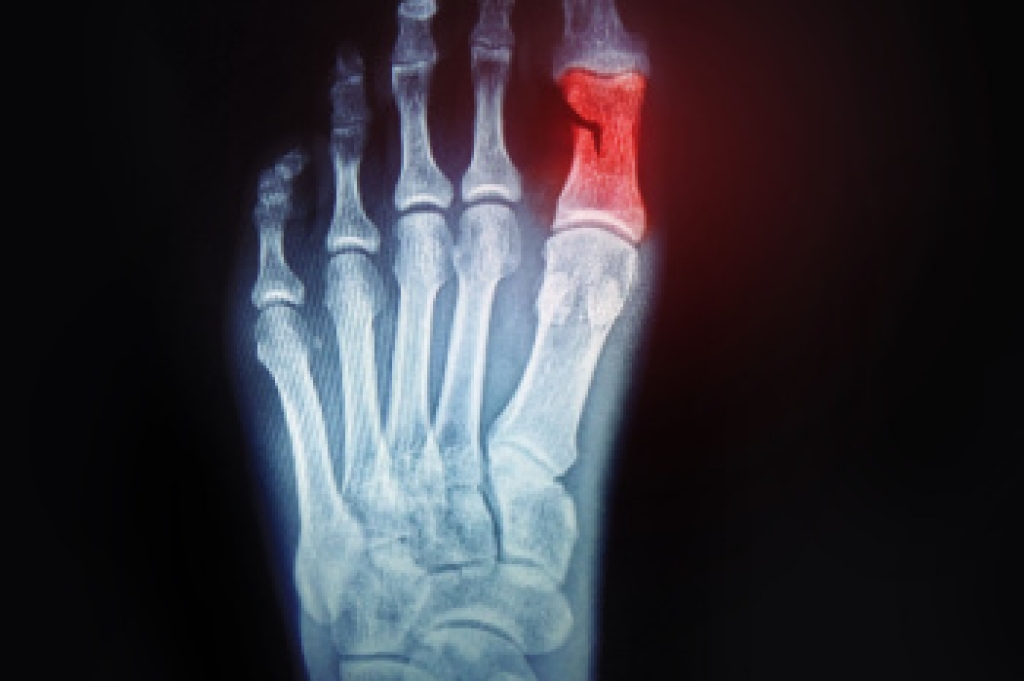

A toe fracture is a break in one or more of the small bones in the toes, usually caused by direct trauma, such as stubbing the toe or dropping a heavy object on the foot. These injuries are common and can vary in severity. Symptoms may include sharp pain, swelling, bruising, and difficulty in walking. In some cases, the toe may appear crooked or deformed. Risk factors include weak bone density, participation in contact sports, and walking barefoot in unsafe areas. A podiatrist can provide a thorough evaluation and determine the best treatment to ensure proper healing. If you think you may have fractured your toe, it is suggested that you consult a podiatrist who can accurately diagnose and treat this injury.

A broken toe occurs when one or more of the toe bones of the foot are broken after an injury. Injuries such as stubbing your toe or dropping a heavy object on it may cause a toe fracture.